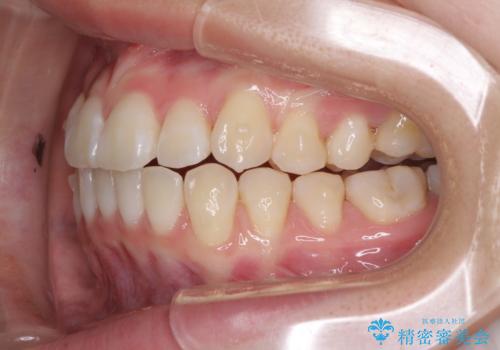

- 海外留学の予定があるが、学生のうちに歯列を整えたいとのことで来院された患者様です。

前歯にデコボコがあり、口元がやや突出した印象があったため、IPR(歯と歯の間を削る)と親知らずを抜歯した上での歯列全体の後方移動をメインに、インビザラインを用いて矯正治療を行うこととしました。